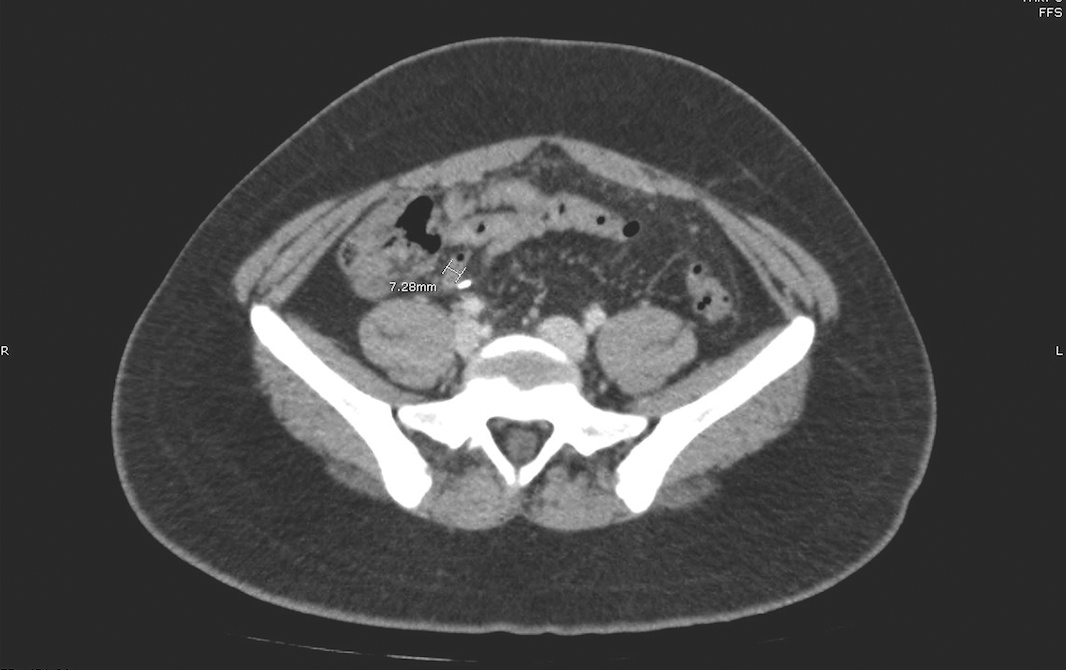

A Teenage Boy With Abdominal Pain After Appendectomy: What Does CT Show?

Daniel Edberg, MD; Rayhan Lal, MD; Cynthia H. Ho, MD

A 16-year-old boy presented to the emergency department with 2 weeks of worsening lower abdominal pain.